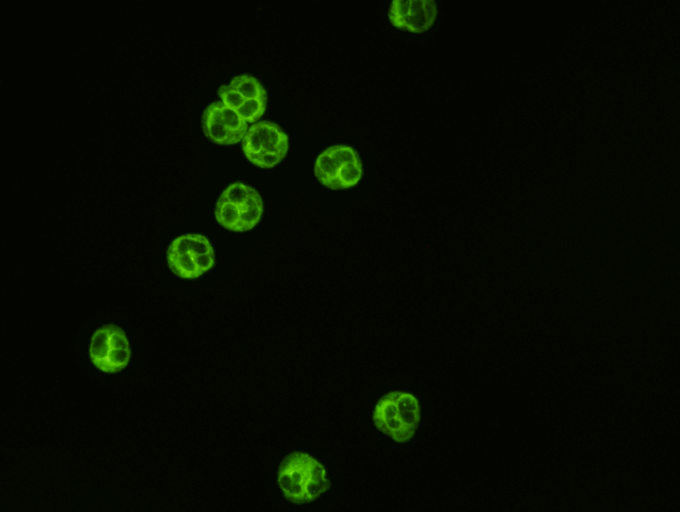

nDNA Antibody (Crithidia luciliae) Test Kit  An indirect Immunofluorescence assay the detection  of antibodies to native dsDNA in human serum utilizing Crithidia luciliae antigen slides.  ANA antibodies are present in theblood of patiences

nDNA Antibody (Crithidia luciliae) Test Kit

An indirect Immunofluorescence assay the detection  of antibodies to native dsDNA in human serum utilizing Crithidia luciliae antigen slides.  ANA antibodies are present in theblood of patiences with certain connective tissue disorders.  SLE patients produce many different types of nuclear antibodies, and those with the specificity for dsDNA have a high correlation with SLE patients.

6050L    50 Test Kit

6100L  100 Test Kit

D500L  500 Test Kit